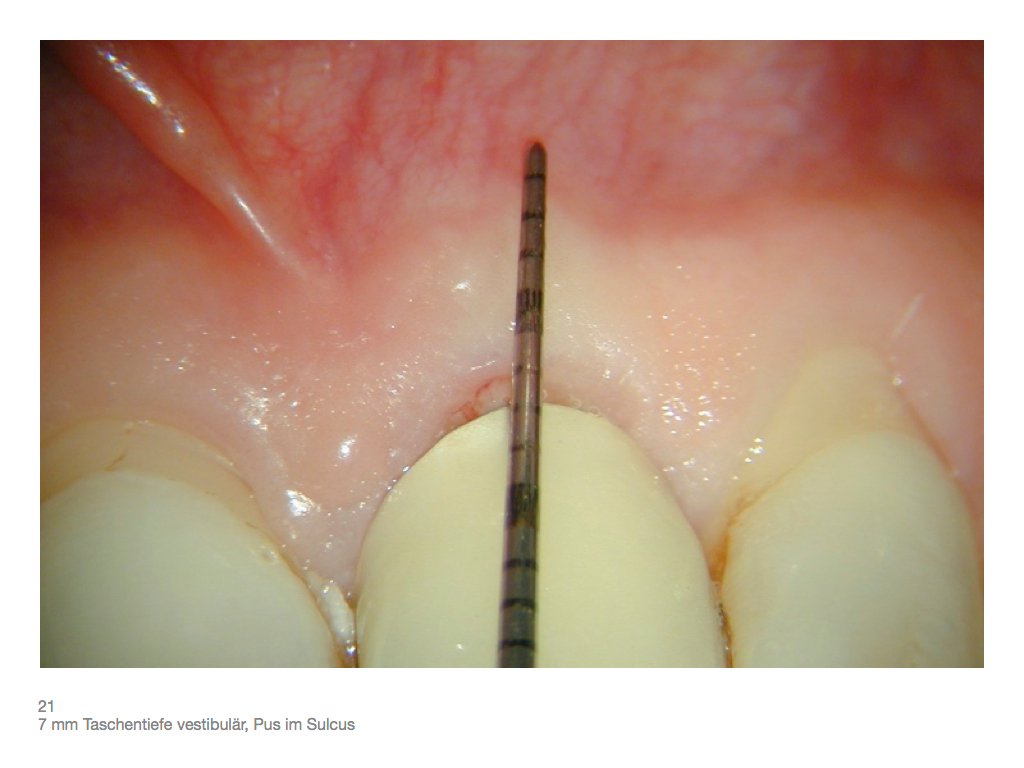

IF.012 Veröffentlicht 3. November 2012 am 1024 × 768 in Zahnerhalt „austherapierter“ Zähne durch endochirurgische Maßnahmen